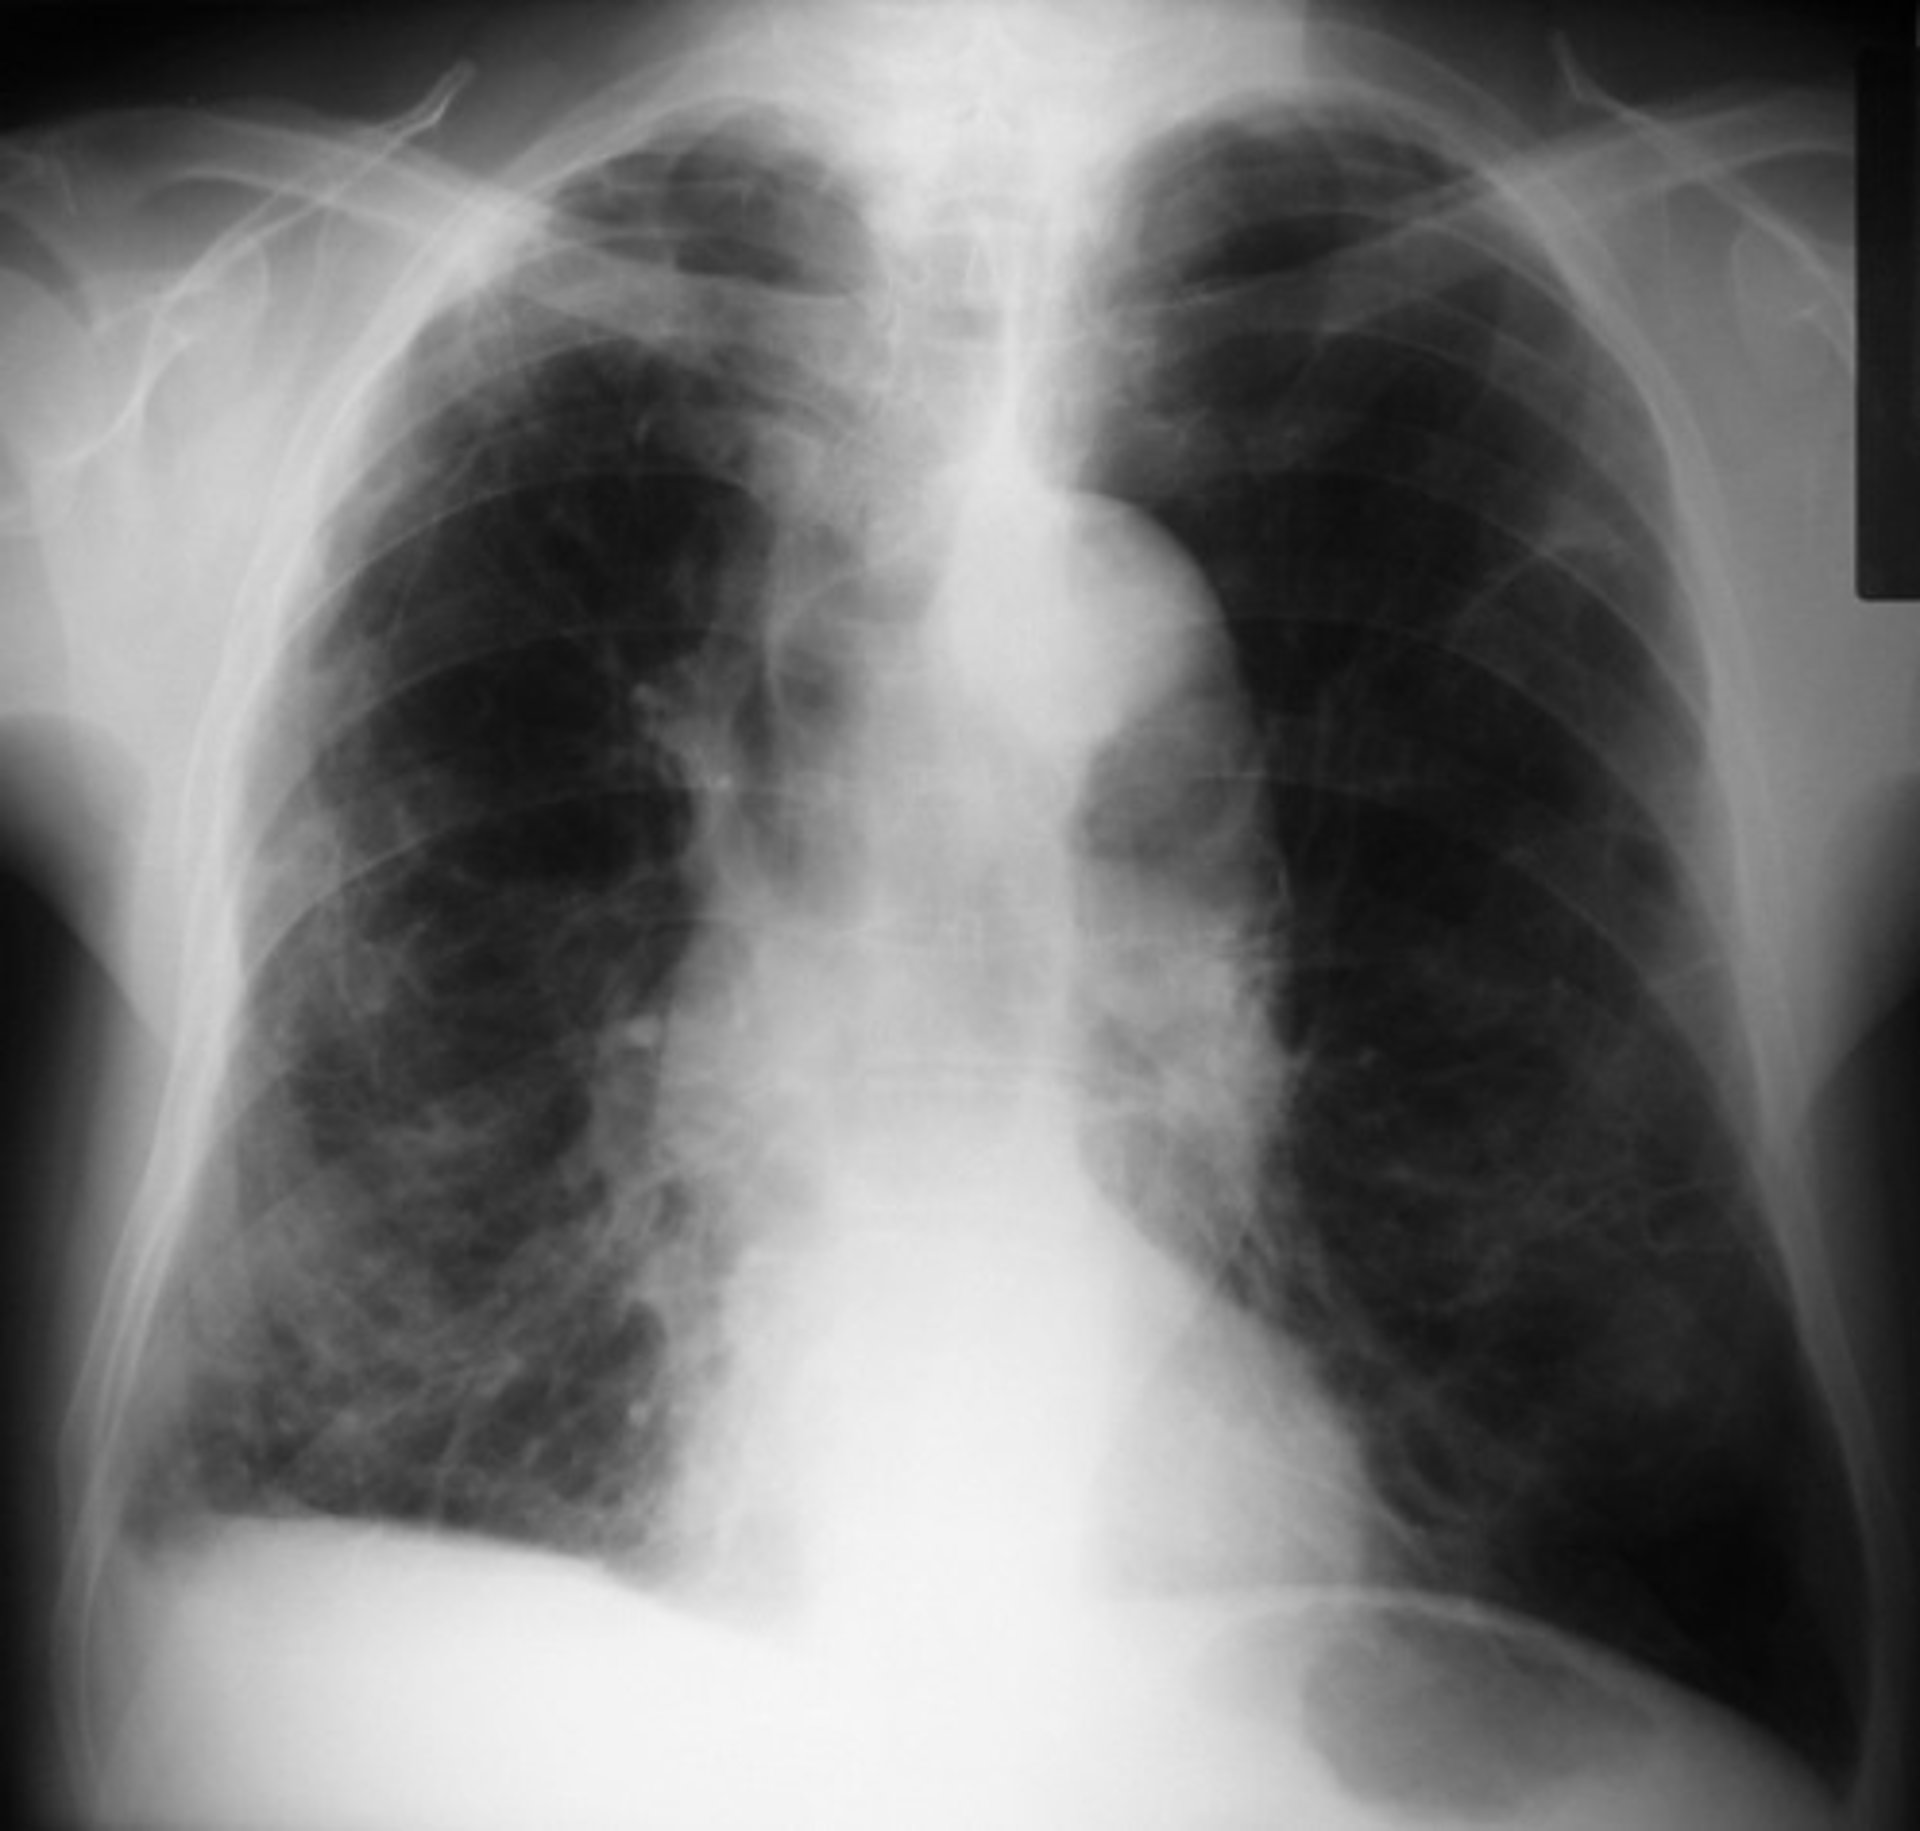

Cuando no influye el tabaco, las mujeres tienen más riesgo de EPOC

EPOC

Un estudio de la Universidad de Toronto (Canadá) ha revelado que las mujeres tienen el doble de riesgo que los hombres de desarrollar una enfermedad pulmonar obstructiva crónica (EPOC) cuando ni unos ni otras son fumadores, pese a que el tabaco es el principal factor desencadenante de esta patología respiratoria.